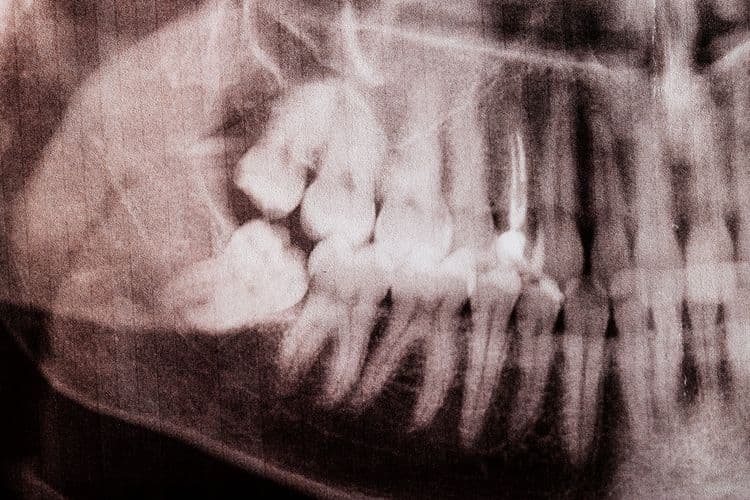

The question of whether alcohol consumption is permissible following wisdom teeth extraction is a common concern among patients. Clinically, it is vital to evaluate the implications of alcohol on the healing process, particularly its potential to disrupt blood clot formation and interact adversely with prescribed analgesics. Understanding the timing and physiological effects of alcohol post-surgery is essential for best recovery. However, can patients afford to risk hindering their recovery by indulging too soon?

Following the extraction of wisdom teeth, the healing process is a complex interplay of biological events that necessitates careful management to guarantee ideal recovery. The healing timeline can vary, typically spanning from several days to a few weeks, contingent upon the individual’s physiological response and adherence to post-surgery care protocols. Initial inflammation is expected within the first 24-48 hours, a vital phase where adherence to prescribed analgesics and anti-inflammatory medications is paramount. Patients are advised to maintain oral hygiene meticulously while avoiding aggressive rinsing or spitting actions. Nutritional intake should be modified to include soft foods, minimizing mechanical irritation. Thorough post-surgery care, including regular monitoring for signs of infection or complications, is essential for optimal tissue regeneration and restoration of oral functionality.